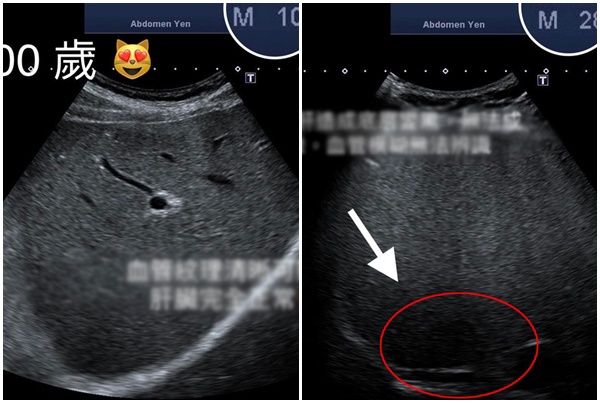

Bác sĩ khoa tiêu hóa và gan mật người Đài Loan Qian Zhenghong chia sẻ gần đây ông đã siêu âm ổ bụng cho một cụ ông 100 tuổi. Điều bất ngờ là khi kiểm tra gan của ông thì hoàn toàn bình thường, không có gan nhiễm mỡ hay dấu hiệu xơ hóa, túi mật cũng ở trạng thái bình thường. Trong khi đó, một thanh niên 28 tuổi mà bác sĩ Qian Zhenghong điều trị dù còn trẻ mà gan đã nhiễm mỡ, siêu âm không thể nhìn rõ hình ảnh lá gan.

Hình ảnh siêu âm gan của cụ ông 100 tuổi (bên trái) trông sáng rõ còn gan của thanh niên 28 tuổi (bên phải) có một vùng tối do gan nhiễm mỡ.